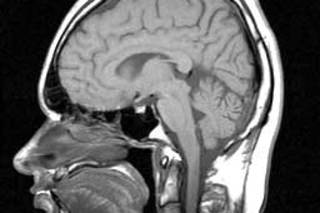

研究人员使用 MRI 扫描并测量了 87 名人类和 69 名黑猩猩的大脑。对于这两个物种,参与者年龄涵盖了成年期的整个寿命范围:人类为 22 至 88 岁,黑猩猩为 10 至 51 岁。(野生黑猩猩很少能活过 45 岁左右;圈养环境下,有些能活到 60 多岁。)

研究人员发现,黑猩猩的大脑区域没有随着年龄显著萎缩。另一方面,人类大脑的每个部分都在萎缩。一些区域——例如额叶,这是负责决策和计划的一个重要区域——到了 80 岁时,体积减少了 25%。

研究人员指出,人类大脑中大多数与年龄相关的萎缩发生在黑猩猩寿命之外——有些发生在生命的第五个十年后期,但大部分发生在第七或第八个十年。

科学家们认为,大脑萎缩可能是我们为额外的几十年寿命付出的代价。我们的大脑消耗巨大的能量——占我们身体总能量的 25%,而黑猩猩仅占 10%——这会随着时间的推移对我们的神经元造成损害。研究的主要作者、人类学家Chet Sherwood告诉 LiveScience.com:“如果你要承担额外 40 年的寿命,并且这些神经元必须发挥作用,最终这似乎将难以维持。”